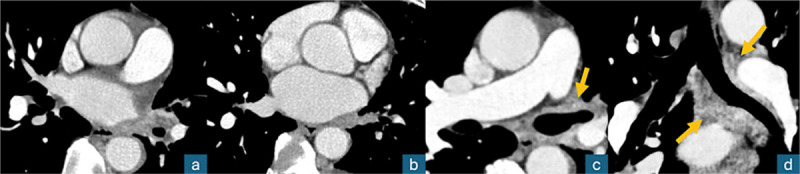

Teaching point: Description of a new radiological sign named "pulmonary hilar cavernoma" in a case of unilateral total pulmonary vein thrombosis.